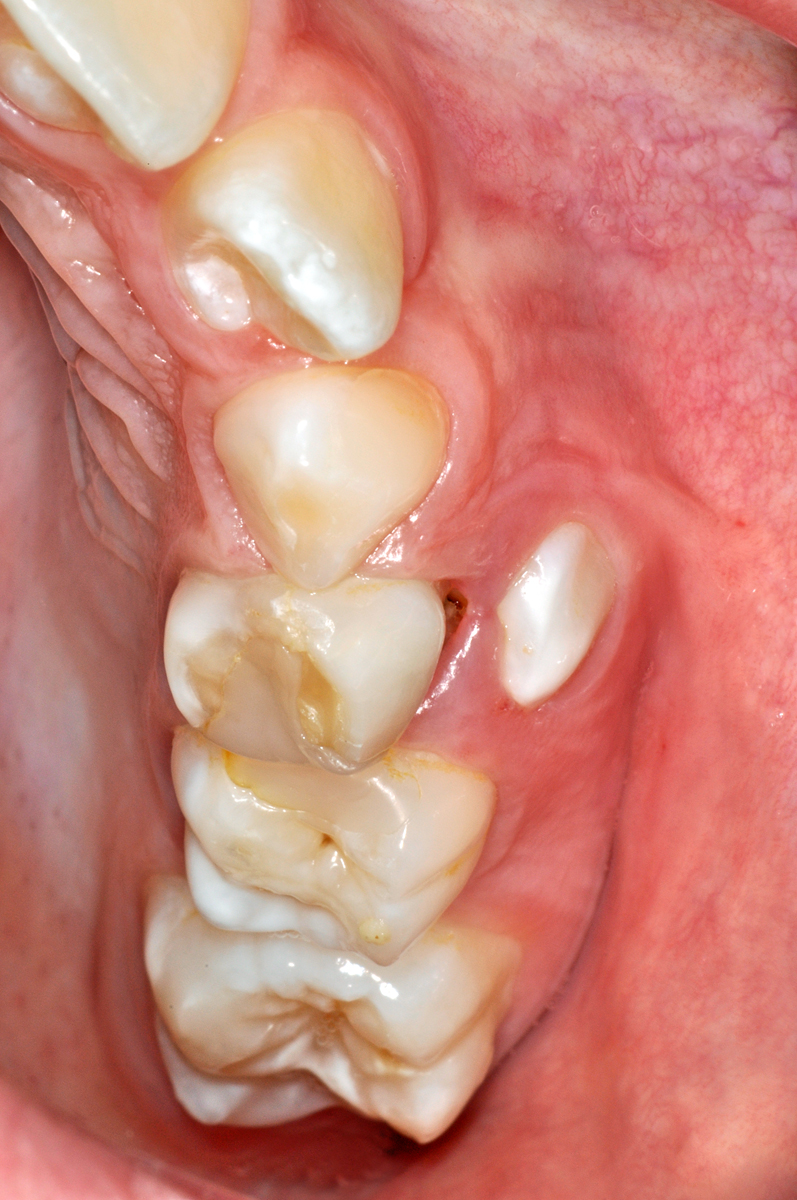

Hier ein Fall, bei dem ein oberer linker kleiner Backenzahn (ein Prämolar, Zahn 24) zu weit aussen und «oben» durchbricht. Dies ist in der Regel kein Problem, sofern der Milchzahn innert vernünftiger Frist (ein bis drei Monate) herausgewackelt werden kann; so löst sich das Problem von selbst.

Oft ist es jedoch so, dass die Milchzähne fest bleiben, weil die gaumenseitige Wurzel nicht genügend aufgelöst wird und den Zahn daher noch hält. Dann kann eine Entfernung des Milchzahnes angezeigt sein, damit sich der bleibende Zahn genügend nach innen bewegen kann und am Schluss am richtigen Platz steht und nicht zu weit aussen am unteren Zahn vorbei durchbricht.

Notfälle sind solche Situationen aber keinesfalls…